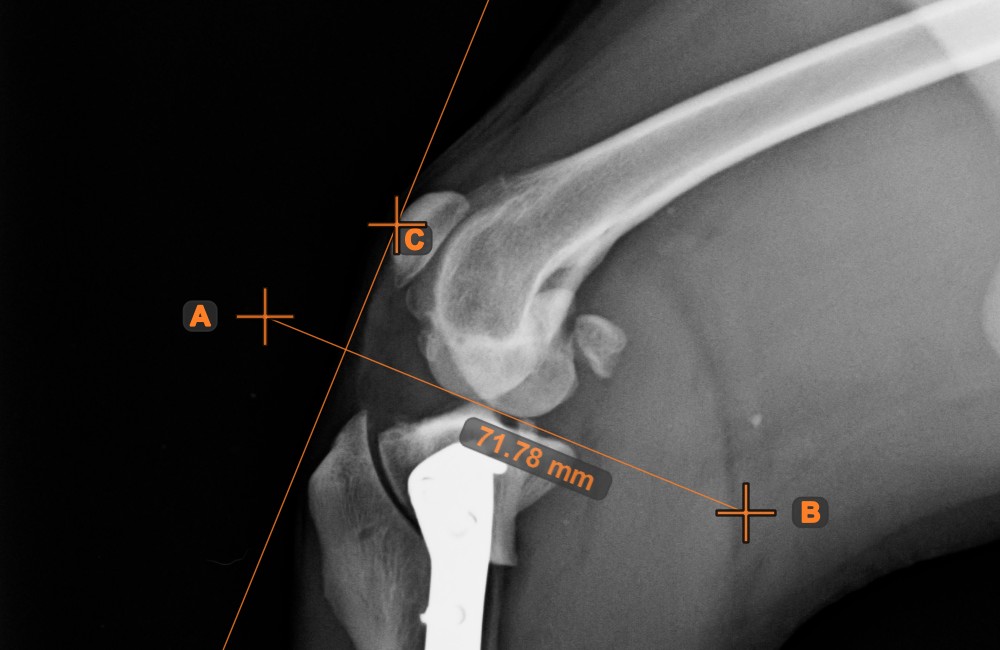

Identify and mark the center point of a new or existing line measurement on the scene by using the Center Point of Line tool.

Select the tool from the left toolbar and assign it to one of the available mouse buttons. Place the start and end points on the scene, select them from already existing points on the image, or select an already drawn line from the scene. The center point of the line will be automatically calculated and placed on the scene. The center point of each line will always be marked with the letter C.